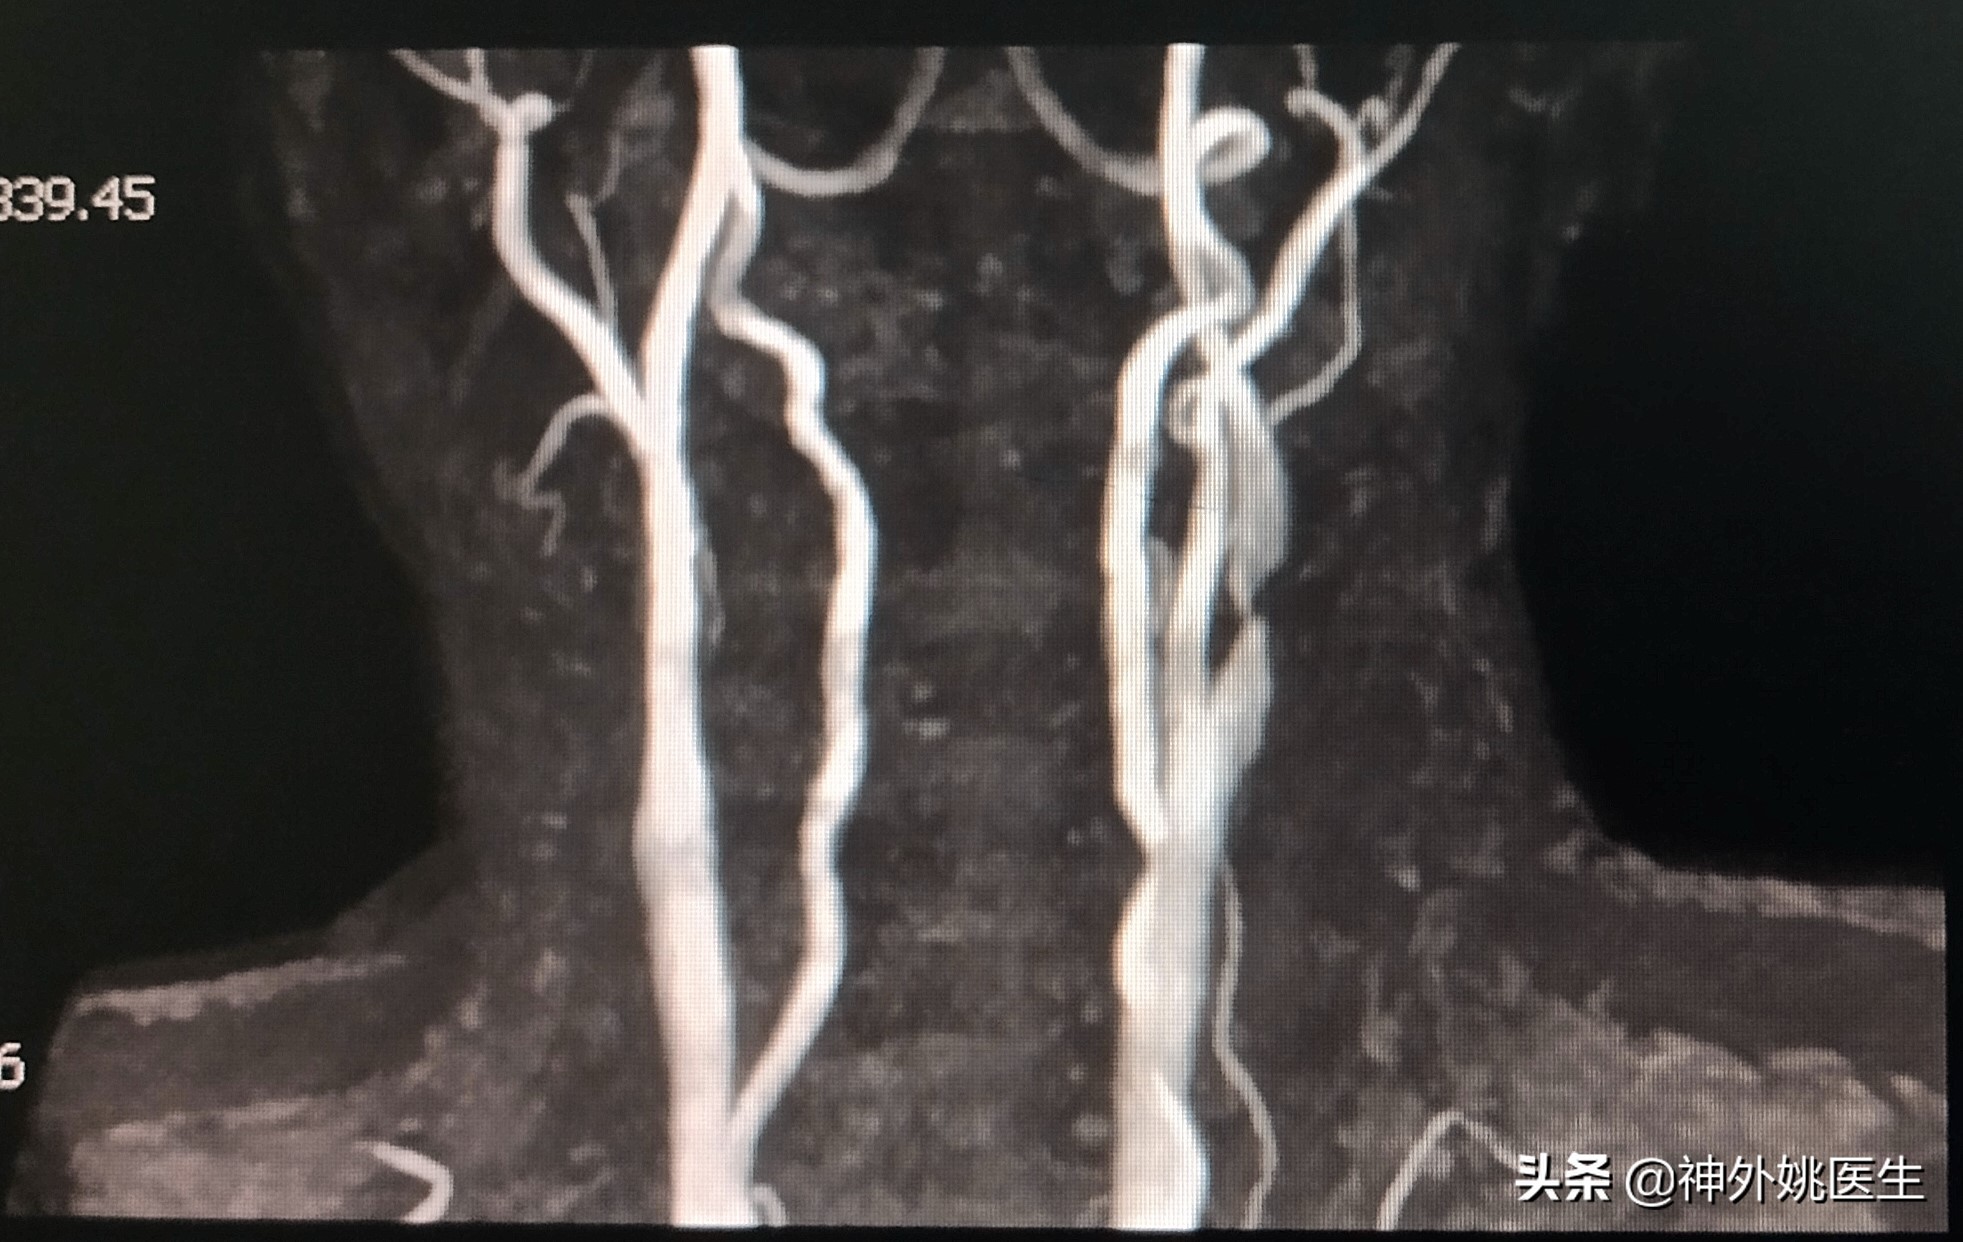

患者廉XX,男性,64岁。主因头痛、头晕,伴右侧肢体无力半年,加重2个月入院。既往“肺腺癌”病史3年,行靶向药物治疗。无“高血压、糖尿病、慢性胃炎”病史。1年前行“腰椎椎体成形手术”。查体:Bp124/91mmHg 神清,语利。双瞳孔正大等圆,对光反射灵敏。左侧肢体肌力5级,右侧肢体肌力5-级。双侧Babinski's征(-)。脑血管彩超示:双侧颈动脉内膜增厚伴斑块形成(多发),左侧颈内动脉起始部狭窄(79-99%)。头MRI+MRA检查:1.双额顶叶及右基底节区缺血灶。2.右颈内动脉虹吸段开窗畸形;左大脑前动脉A1段稍纤细。(图1)颈椎CT示:1、颈椎多发异常密度影,考虑转移瘤;2、颈5/6椎间盘左后突出,椎管狭窄;颈椎骨质增生,排列不稳;4、项韧带钙化。颈部MRI+MRA检查示:1、颈3/4、4/5、5/6、6/7椎间盘突出。2、颈3/4、6/7水平水平椎管狭窄。3、颈椎骨质增生。4、左侧颈内动脉起始部狭窄。(图2)

图2 颈部MRA示左侧颈内动脉起始部狭窄。